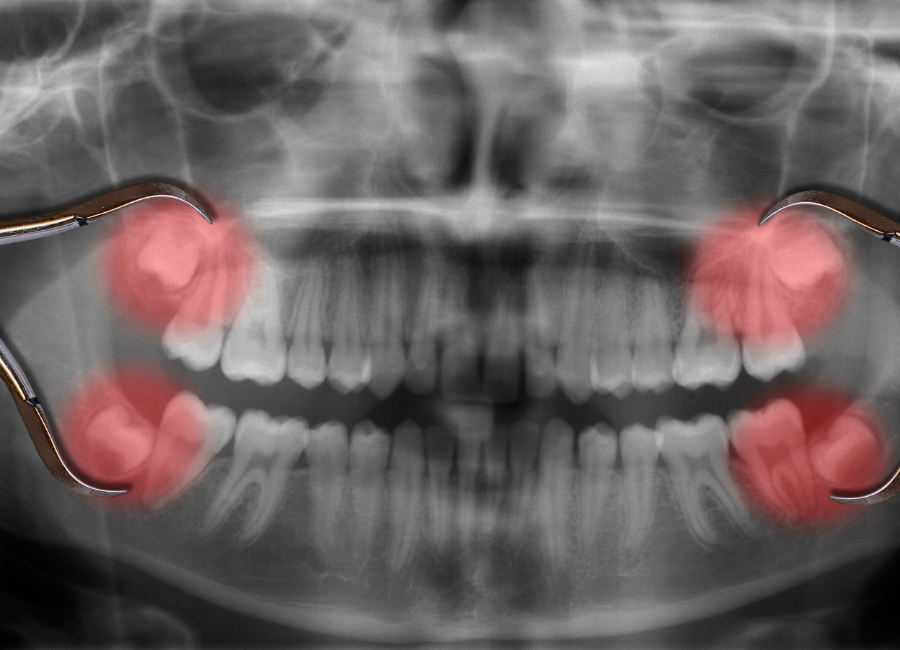

Wisdom teeth are situated right at the back of your mouth. This is also known as the third molar teeth. They are called wisdom teeth because they tend to grow or erupt in the teenage years and early twenties. Some wisdom teeth never actually fully form (partly erupt) and can even get stuck against nearby teeth or bones.

This can cause issues and even leave a flap of gum over your tooth. Wisdom teeth vary for so many people and can even grow too long in some cases. Some people never have any issues with their wisdom teeth at all!